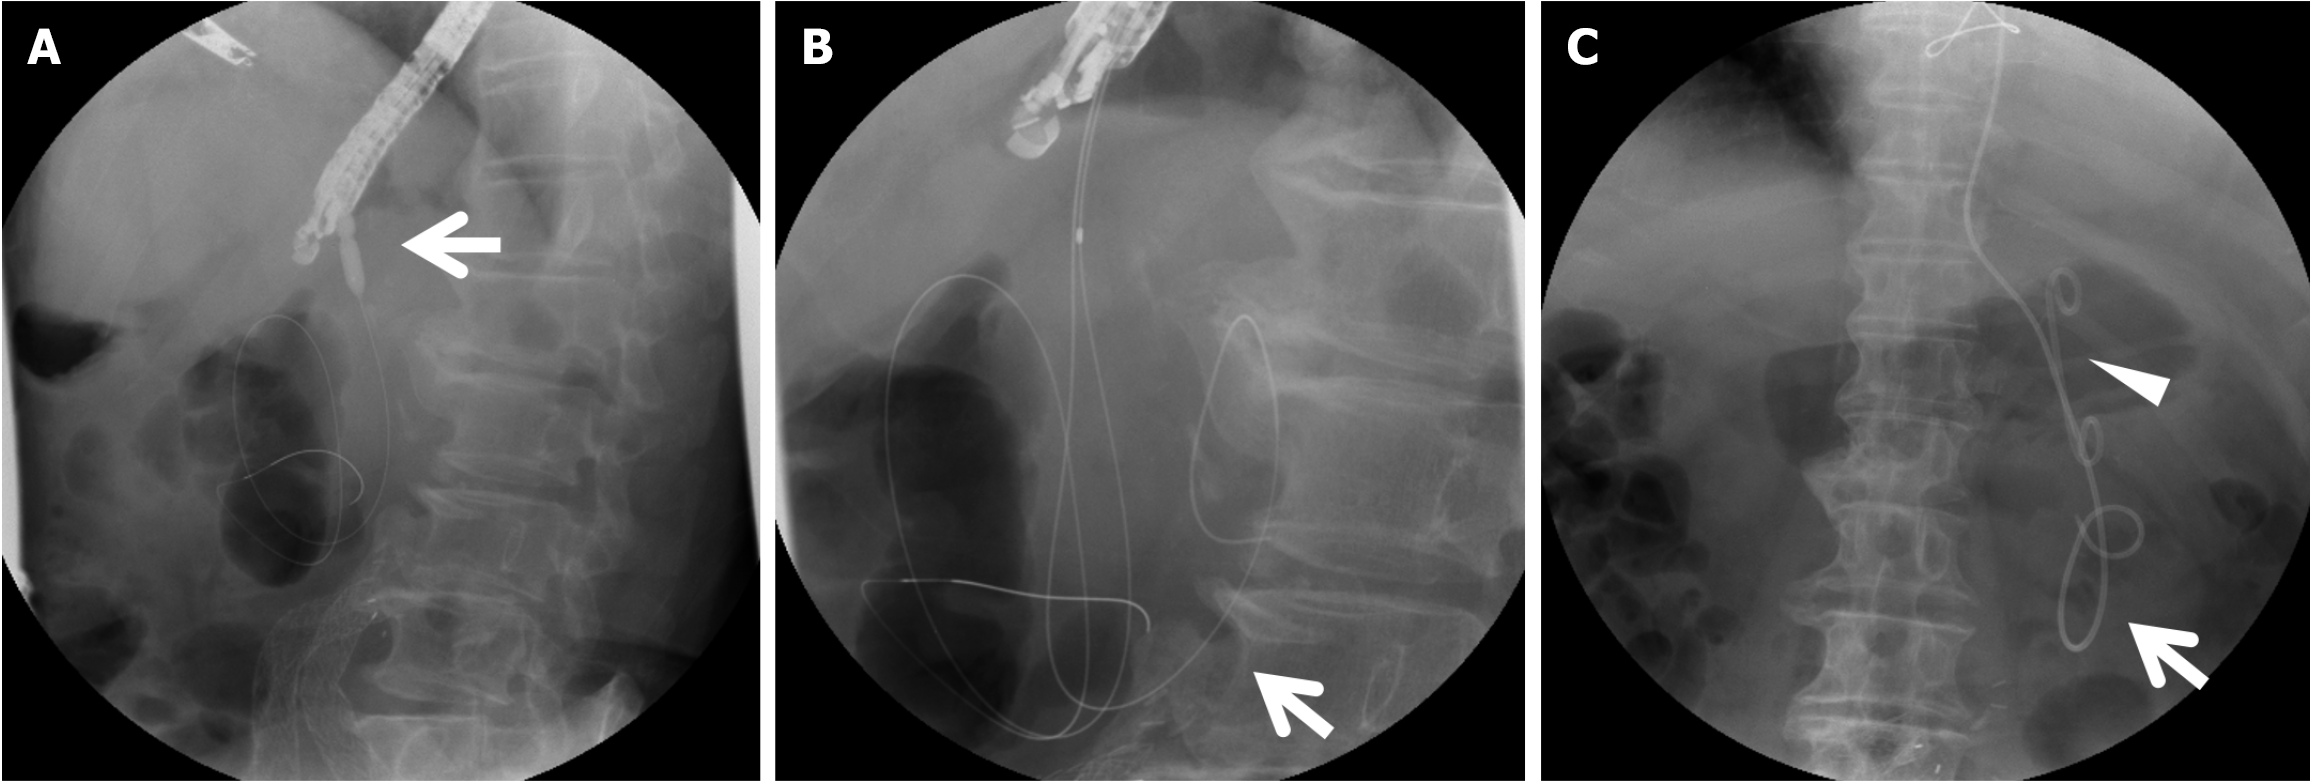

Figure 3 Endoscopic drainage of walled-off necrosis on postoperative day 50.

A: Dilation of the puncture site of a gastric wall using a dilation balloon (arrow); B: Additional wire (arrow) insertion; C: Double pig tail plastic stent (arrowhead) and pigtail nasal drainage tube (arrow) placement.